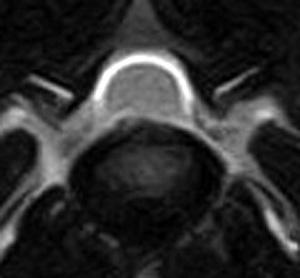

5~6歳以上の去勢手術をしていないオス犬に多い病気ですが、メス犬や去勢した犬に起こることもあります。お尻の筋肉が萎縮した結果、筋肉の隙間から直腸や膀胱が皮膚の下にとびでてしまいます。これにより便が出にくくなったり膀胱炎になったりします。手術をすることで機能回復および今後の致死的な状況を回避することができます。当院では去勢手術→結腸固定→前立腺固定→骨盤隔膜構成筋の縫縮→内閉鎖筋フラップ→浅臀筋フラップの順で通常腹側・臀部左右両側同時に行います。また老化以外に、筋肉が萎縮する原因があったり、腹圧がかかる原因があったりする場合も多いので、再発防止のためそれらの診断・治療も重要です。今回のワンちゃんも無事手術も終わり元気に退院しました。よかったね。